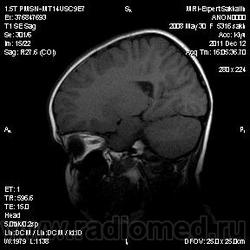

Девочка 3 года.В анамнезе -родовая травма-внутрижелудочковые кровоизлияния 1-2 ст.Задержка психического развития.Со слов мамы, "бывают истерики, хватается ручками за голову, особенно затылочную часть".Как интерпретировать изменения в желудочках, в задних рогах?Ликворную кисту ЗЧЯ отметила.

Киста не совсем киста, но нижняя ретроцеребеллярная цистерна незначительно расширена- я указала.

Здравствуйте! Извините что вклиниваюсь в вашу дискуссию. В дополнение ко всему сказанному мне показалось что для трехлетнего ребенка желудочки несколько великоваты, больше слева. Ликворные пространства не симметричны, опять больше слева. В складочках мозга мелкие, пока, кисточки. Может быть попробовать исключить церебральный арахноидит? Пункцию делали?

Коллеги, в рамках ликбеза: а такое (некоторое) расширение субарахноидального пространства (не вполне характерное для 3-летнго ребенка), расценивается как гидроцефалия (заместительная, открытая, последствие ишемически-гипоксического синдрома) или нет?